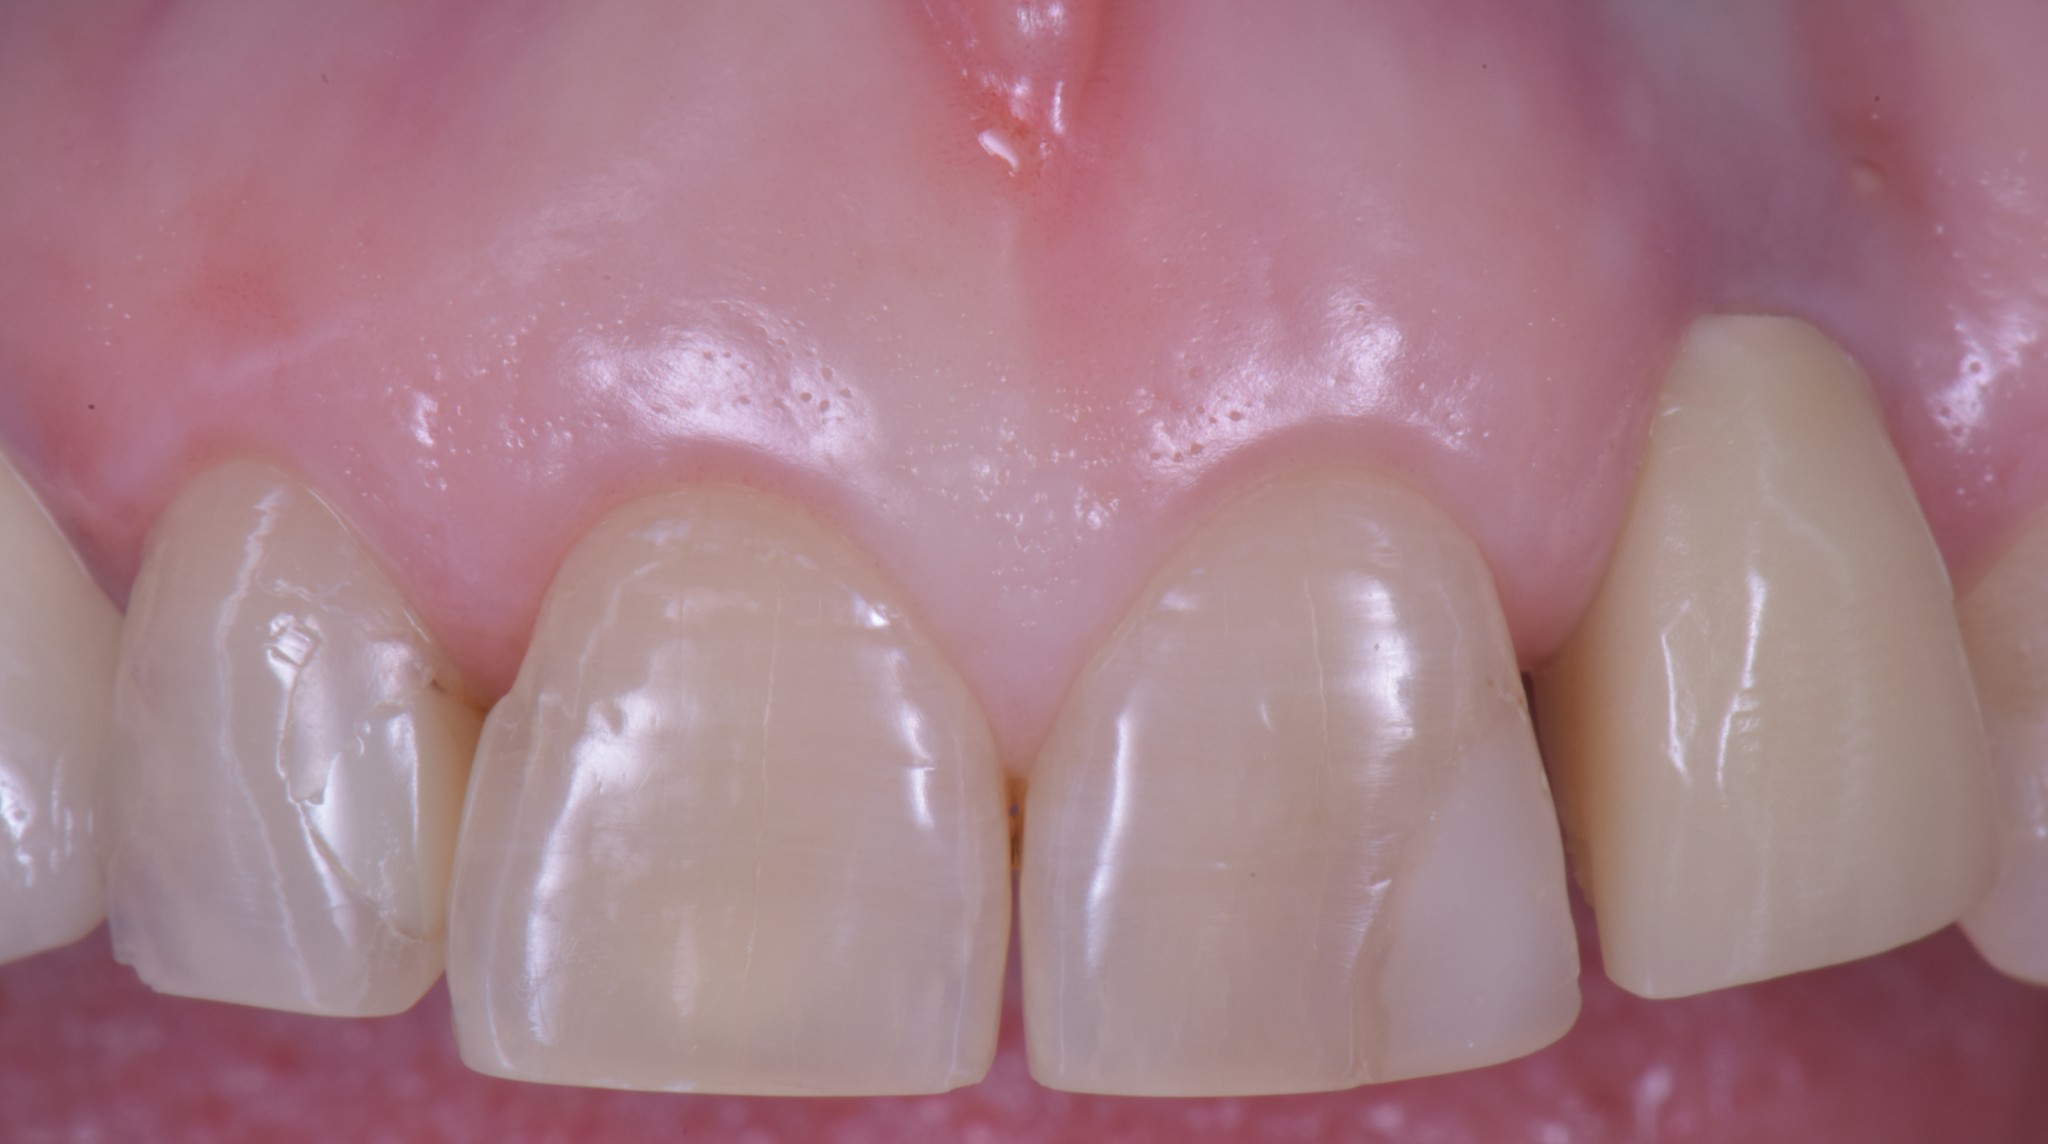

corso gestione tessuti molli - guarigione 1

corso gestione dei tessuti molli - guarigione 2

Ti mostro la foto a sette giorni per due motivi.

• La bellezza di una chirurgia si valuta dalla guarigione a sette giorni. Se aspetti 2 anni, alla fine anche una chirurgia di merda guarisce.

• Ho operato la paziente 7 giorni fa e non ho foto più recenti ma penso che concorderai con me che dopo una guarigione così difficilmente avremo delle sorprese.

Come puoi vedere abbiamo risolto completamente il deficit dei tessuti molli che era stato lasciato dopo le precedenti terapie e…

… posto le basi per una nuova riabilitazione definitiva che si possa definire esteticamente degna dei tempi in cui abbiamo la fortuna di vivere.